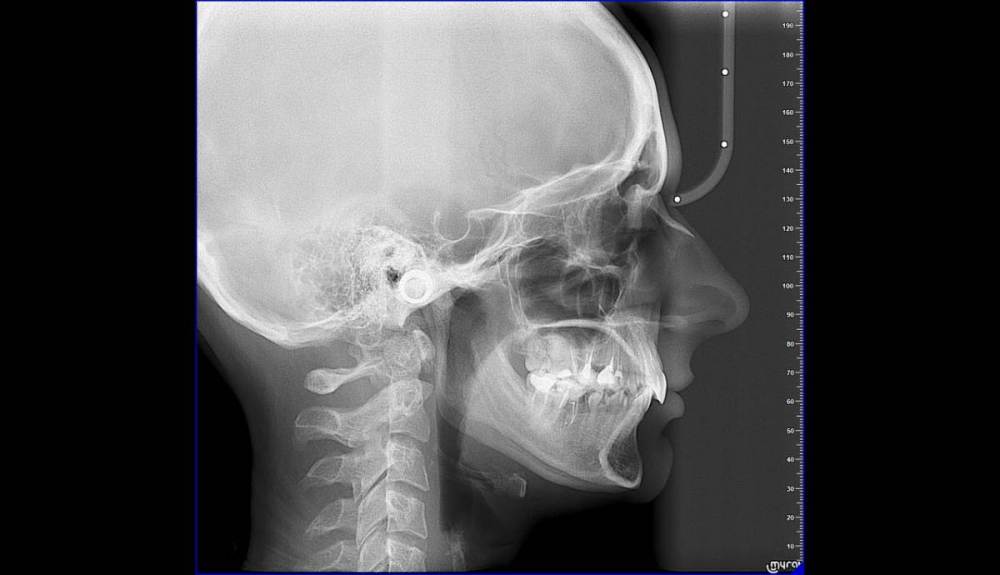

Очень давно, в 2010-2012гг после удаления 26 и 46 зубов челюсть начала заедать и щелкать.

Сейчас я обратилась к ортодонтам с целью выровнять только нижний зубной ряд (искривлен из за воздействия 8ок), с последующей установкой импланта (46 зуб). Нижние восьмерки удалены.

26 отсутствует, 27 стоит на месте 26, 28 стоит на месте 27

11 сломан в корне, держится на штифте + пломба соединяющая его с соседними зубами.

15-16 зуб - черная дыра - что это может быть? Есть ли шансы спасти?